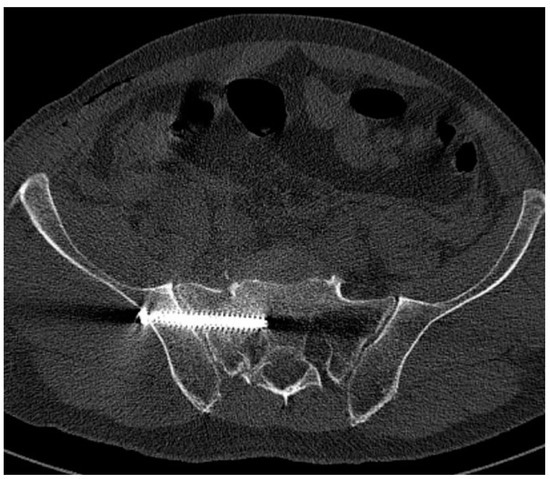

Differences in Accuracy and Radiation Dose in Placement of Iliosacral Screws: Comparison between 3D and 2D Fluoroscopy

3.3. Operative Time

4.2. Screw Positioning